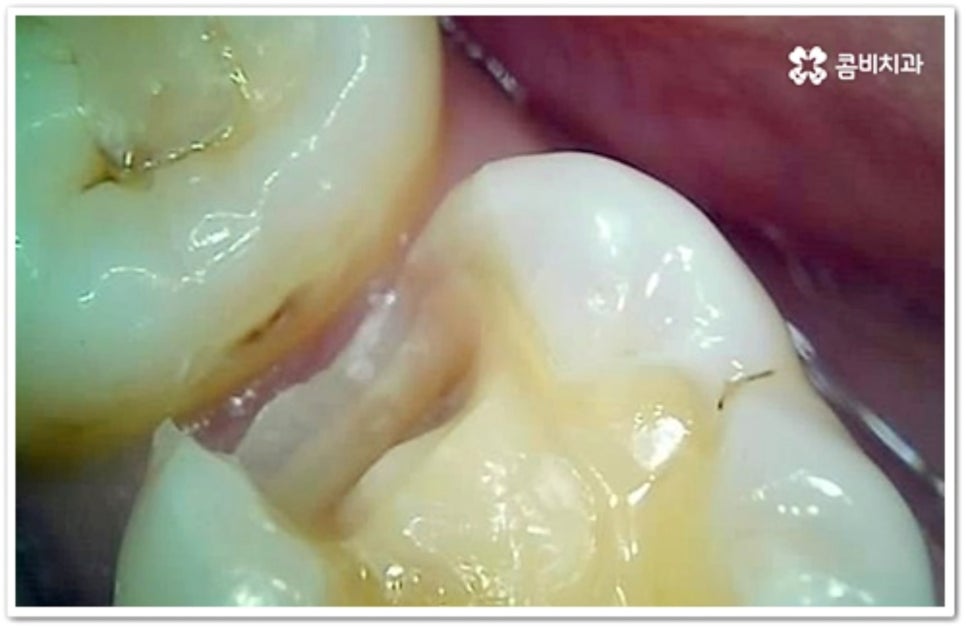

충치는 시간을 두고 단계적으로 진행하는 구강 질환이기 때문에 초기에 발견하여 빠르게 대처해 주는 것이 구강 건강을 위해 보다 바람직한 방법이라 할 수 있습니다. 흔히 우리가 충치라고 부르는 치아 우식증은 발생 위치에 따라 두 가지 종류로 나눌 수 있는데요. 보통 위아래 치아가 마주보는 교합면에 생기는 충치는 육안으로 발견할 가능성이 높고 접근이 용이하기 때문에 치료가 쉬운 편이지만, 치아 사이에 생기는 인접면 충치 는 맞닿은 치아로 인해 노출이 잘 되지 않기 때문에 발견도 어렵고 상황에 따라 치료할 때 기구를 손상 부위까지 닿게 하기 위해 치아 삭제가 많이 이루어져야 하는 경우도 있는 등 좀 더 까다로울 수 있어요.

하지만 앞니가 아닌 안쪽 어금니의 인접면 충치 라면 증상이 없고 발견이 쉽지 않기 때문에 초기에 발견하고 치료를 하는 것이 힘들 수 있어요. 그렇기 때문에 평상시에 꾸준히 검진을 받고 치실을 사용하여 칫솔질을 꼼꼼하게 해 주는 것이 더욱 중요한 거예요.

인접면에 충치가 생겼을 때 치료 과정은 손상 정도에 따라 달라질 수 있는데 만약 아주 경미하다면 바로 레진으로 이를 수복할 수 있겠지만 치아 경계면이 무너졌다면 직접적인 레진 수복으로는 생리학적 형태를 재현하기 까다롭기 때문에 본을 떠서 외부에서 금이나 세라믹 보철물을 만들어 끼워넣는 간접적인 방법을 통해 도움을 받을 수 있어요. 환자분들의 상황에 따라 치아 일부만 수복해야 할 때는 인레이 치료를 하고 손상이 크면 신경치료를 한 후 필요시 내부에 기둥을 세우고 치아 전체를 다듬어 씌우는 크라운 치료를 이용하게 될 거예요.